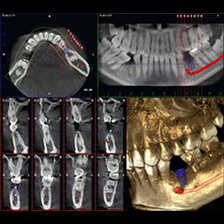

歯科用CT

CT(Computed Tomography)とは、コンピューター断層撮影を意味します。CTは、X線とコンピューターによって、歯や骨の位置や形態などを立体的(3D)に撮影することができます。

血管や神経の位置を立体的に把握し、骨量、骨密度を正確に確認できるため、インプラント治療の際にはCTによる診査・診断が必須となっています。

また、CTは、インプラント治療だけでなく、さまざまな歯科治療の精度向上に役立ちます。歯、血管、神経の位置だけでなく、歯槽骨の状態や根管の形態等もより正確に把握することができるため、埋伏歯抜歯、矯正治療、根管治療、歯周病治療などで、より正確な診査・診断、治療の予知性を高度化を実現することができます。